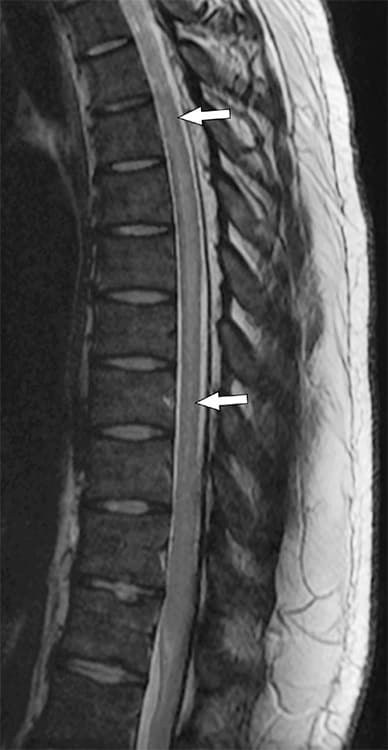

يُبين التصوير بالرنين المغناطيسي السهمي بمرجحة T2 للعمود الفقري الصدري وجود آفة طولية بالحبل الشوكي ذات كثافة مُفرطة بمرجحة T2 (الأسهم).